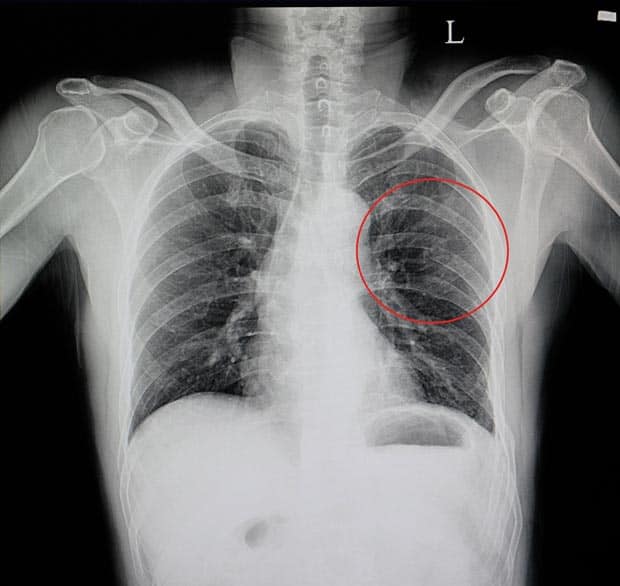

• Лучевые исследования. Рентгенография позволяет выявить участки инфильтрации легочной ткани через несколько дней после травмы. Она необходима при подозрении на перелом ребер, пневмо- и гемоторакс. Компьютерная томография рекомендуется при более тяжелых патологиях, таких как разрыв легкого, пневмоцеле и ателектазы.